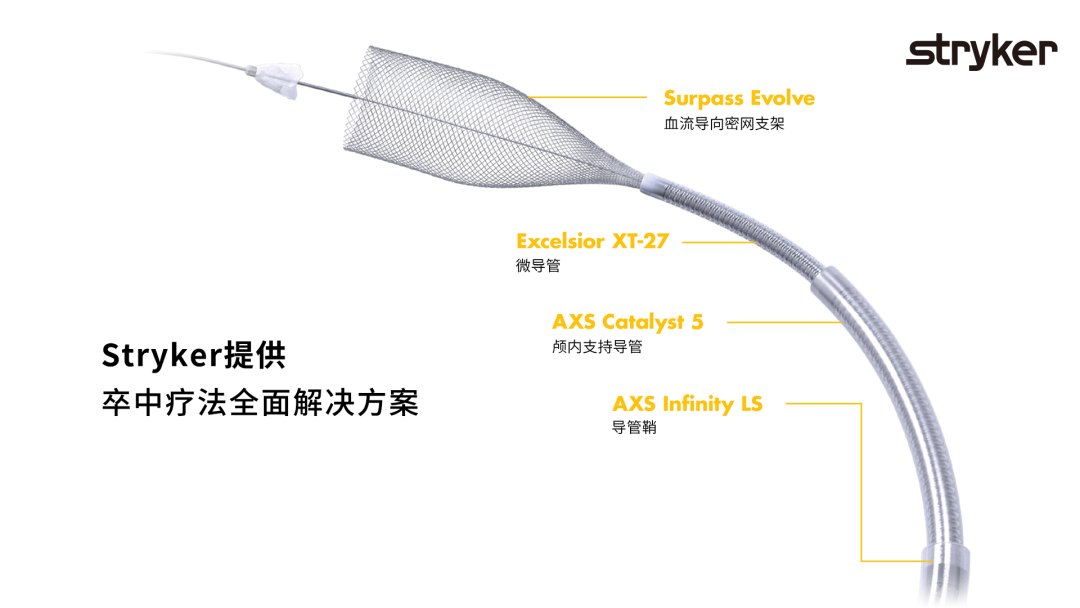

长鞘:90cm

中间导管:6F 115cm

密网支架:FD Surpass Evolve 3.25mm*15mm

弹簧圈微导管:SL-10 with Synchro2 Standard

支架微导管:XT-27 with Synchro2 Standard

弹簧圈:Target 1.0mm*2mm